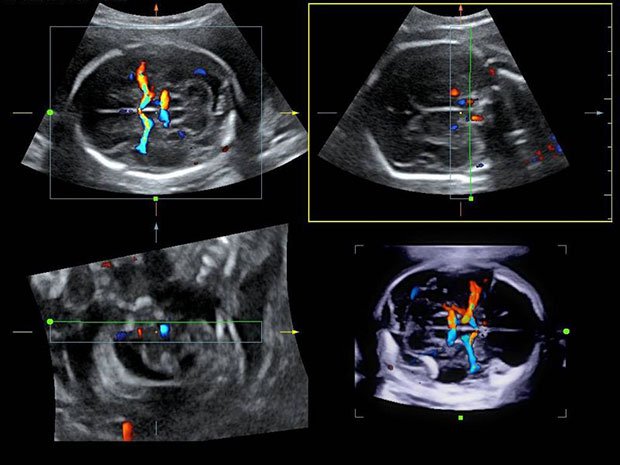

УЗ-исследования детей с первых дней жизни.

УЗИ новорожденных и детей до 1 года позволяет получить точную информацию о состоянии внутренних органов, головного мозга, тазобедренных суставов, помогает оценить последствия родовой травмы, выяснить причины аномальной формы головы, выявить пороки развития ребенка.